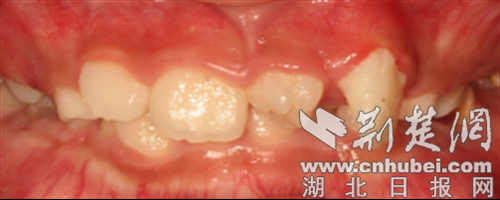

多生牙堵住新牙萌出通道。 通讯员 供图

挤占正常牙齿空间:导致恒牙萌出位置异常,出现牙齿排列拥挤、不齐。

影响颌骨发育:埋伏在颌骨内的多生牙,可能压迫周围牙根,导致牙根吸收(牙齿变松),严重时还会影响颌骨的正常生长,造成面部不对称。